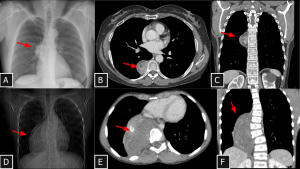

Fig 16: Case 17 – Paravertebral hematoma in trauma:

A 27-year-old patient who sustained a 10-meter fall presented with multiple vertebral body fractures from T8 to T11 (arrows in C) and a large paravertebral mediastinal hematoma extending from T5 to T11 (B), causing anterior displacement of visceral mediastinal structures. An arterial focus of active bleeding was identified (arrows in A).

SYSTEMATIC APPROACH: 1. Age: Any (Trauma/Coagulopathy). | 2. Morphology: High attenuation on CT (50–70 HU) in acute phase. | 3. Enhancement: None (except active extravasation). | 4. Relevant Anatomical Relationships: Paravertebral; displaces mediastinal pleura laterally (extra-pleural sign).